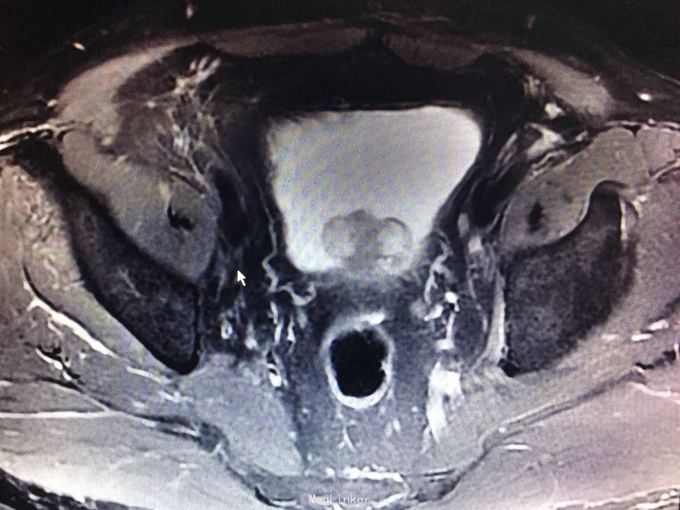

肉眼血尿一周余。 患者一周前无明显诱因出现肉眼血尿。遂于我院就诊,门诊膀胱镜提示:膀胱左侧巨大占位,未窥及基底部。今为进一步治疗收入我科。 九年前于上海行膀胱部分切除术。 81岁,男性患者

查体:无殊。 门诊MRI提示膀胱多发肿瘤,累及深肌层。